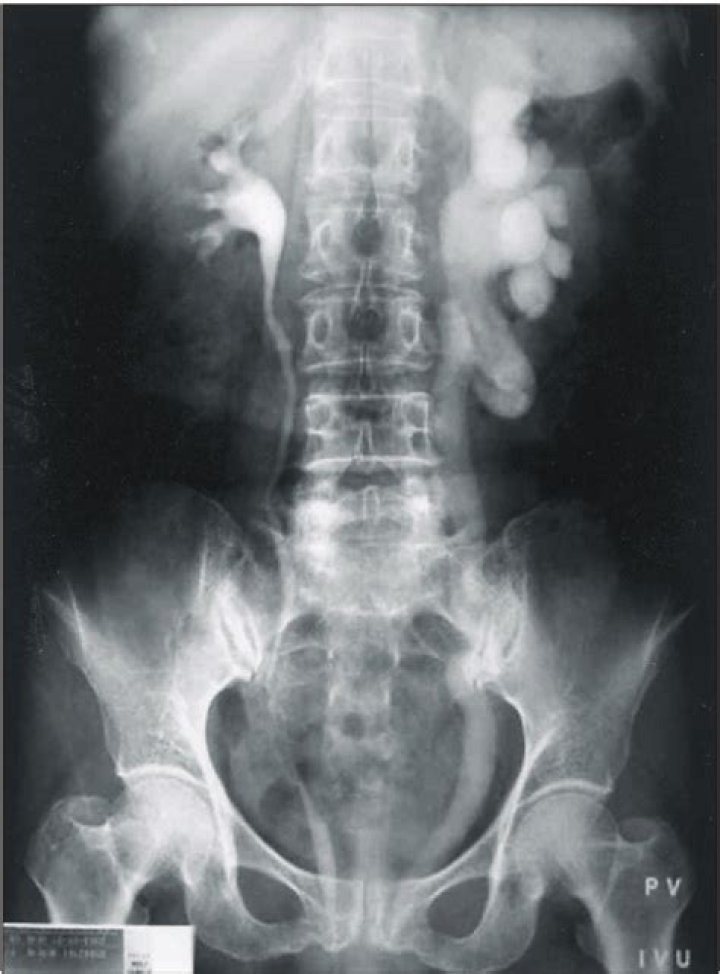

Unilateral hydronephrosis is found on an imaging test such as: